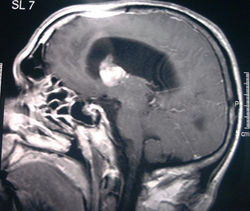

Patologie Endocraniche

di Interesse Neurochirurgico

Le principali malattie endocraniche di interesse neurochirurgico sono di origine:

- Tumorale

- Malformativa

- Degenerativa

e riguardano in genere l'asportazione di masse in accrescimento che comprimono o danneggiano il cervello.

Tali masse possono essere di natura tumorale oppure possono essere ematomi o emorragie che invadono l'encefalo.